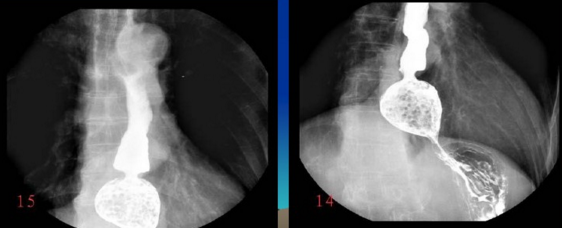

很多人没有接触到数字胃肠一体机,可能对它还比较陌生。其实它是一款多功能数字造影胃肠机,功能强大,操作便捷,可以真正实现数字化摄影,以及无胶片化管理,配置先进的工作站,可以保证其图像画质。同时它在临床上的应用也比较的广泛,能够检查多种疾病。下面,由普爱医疗小编详细列举一些。

2、选择性小肠造影。

3、气钡双重对比造影。